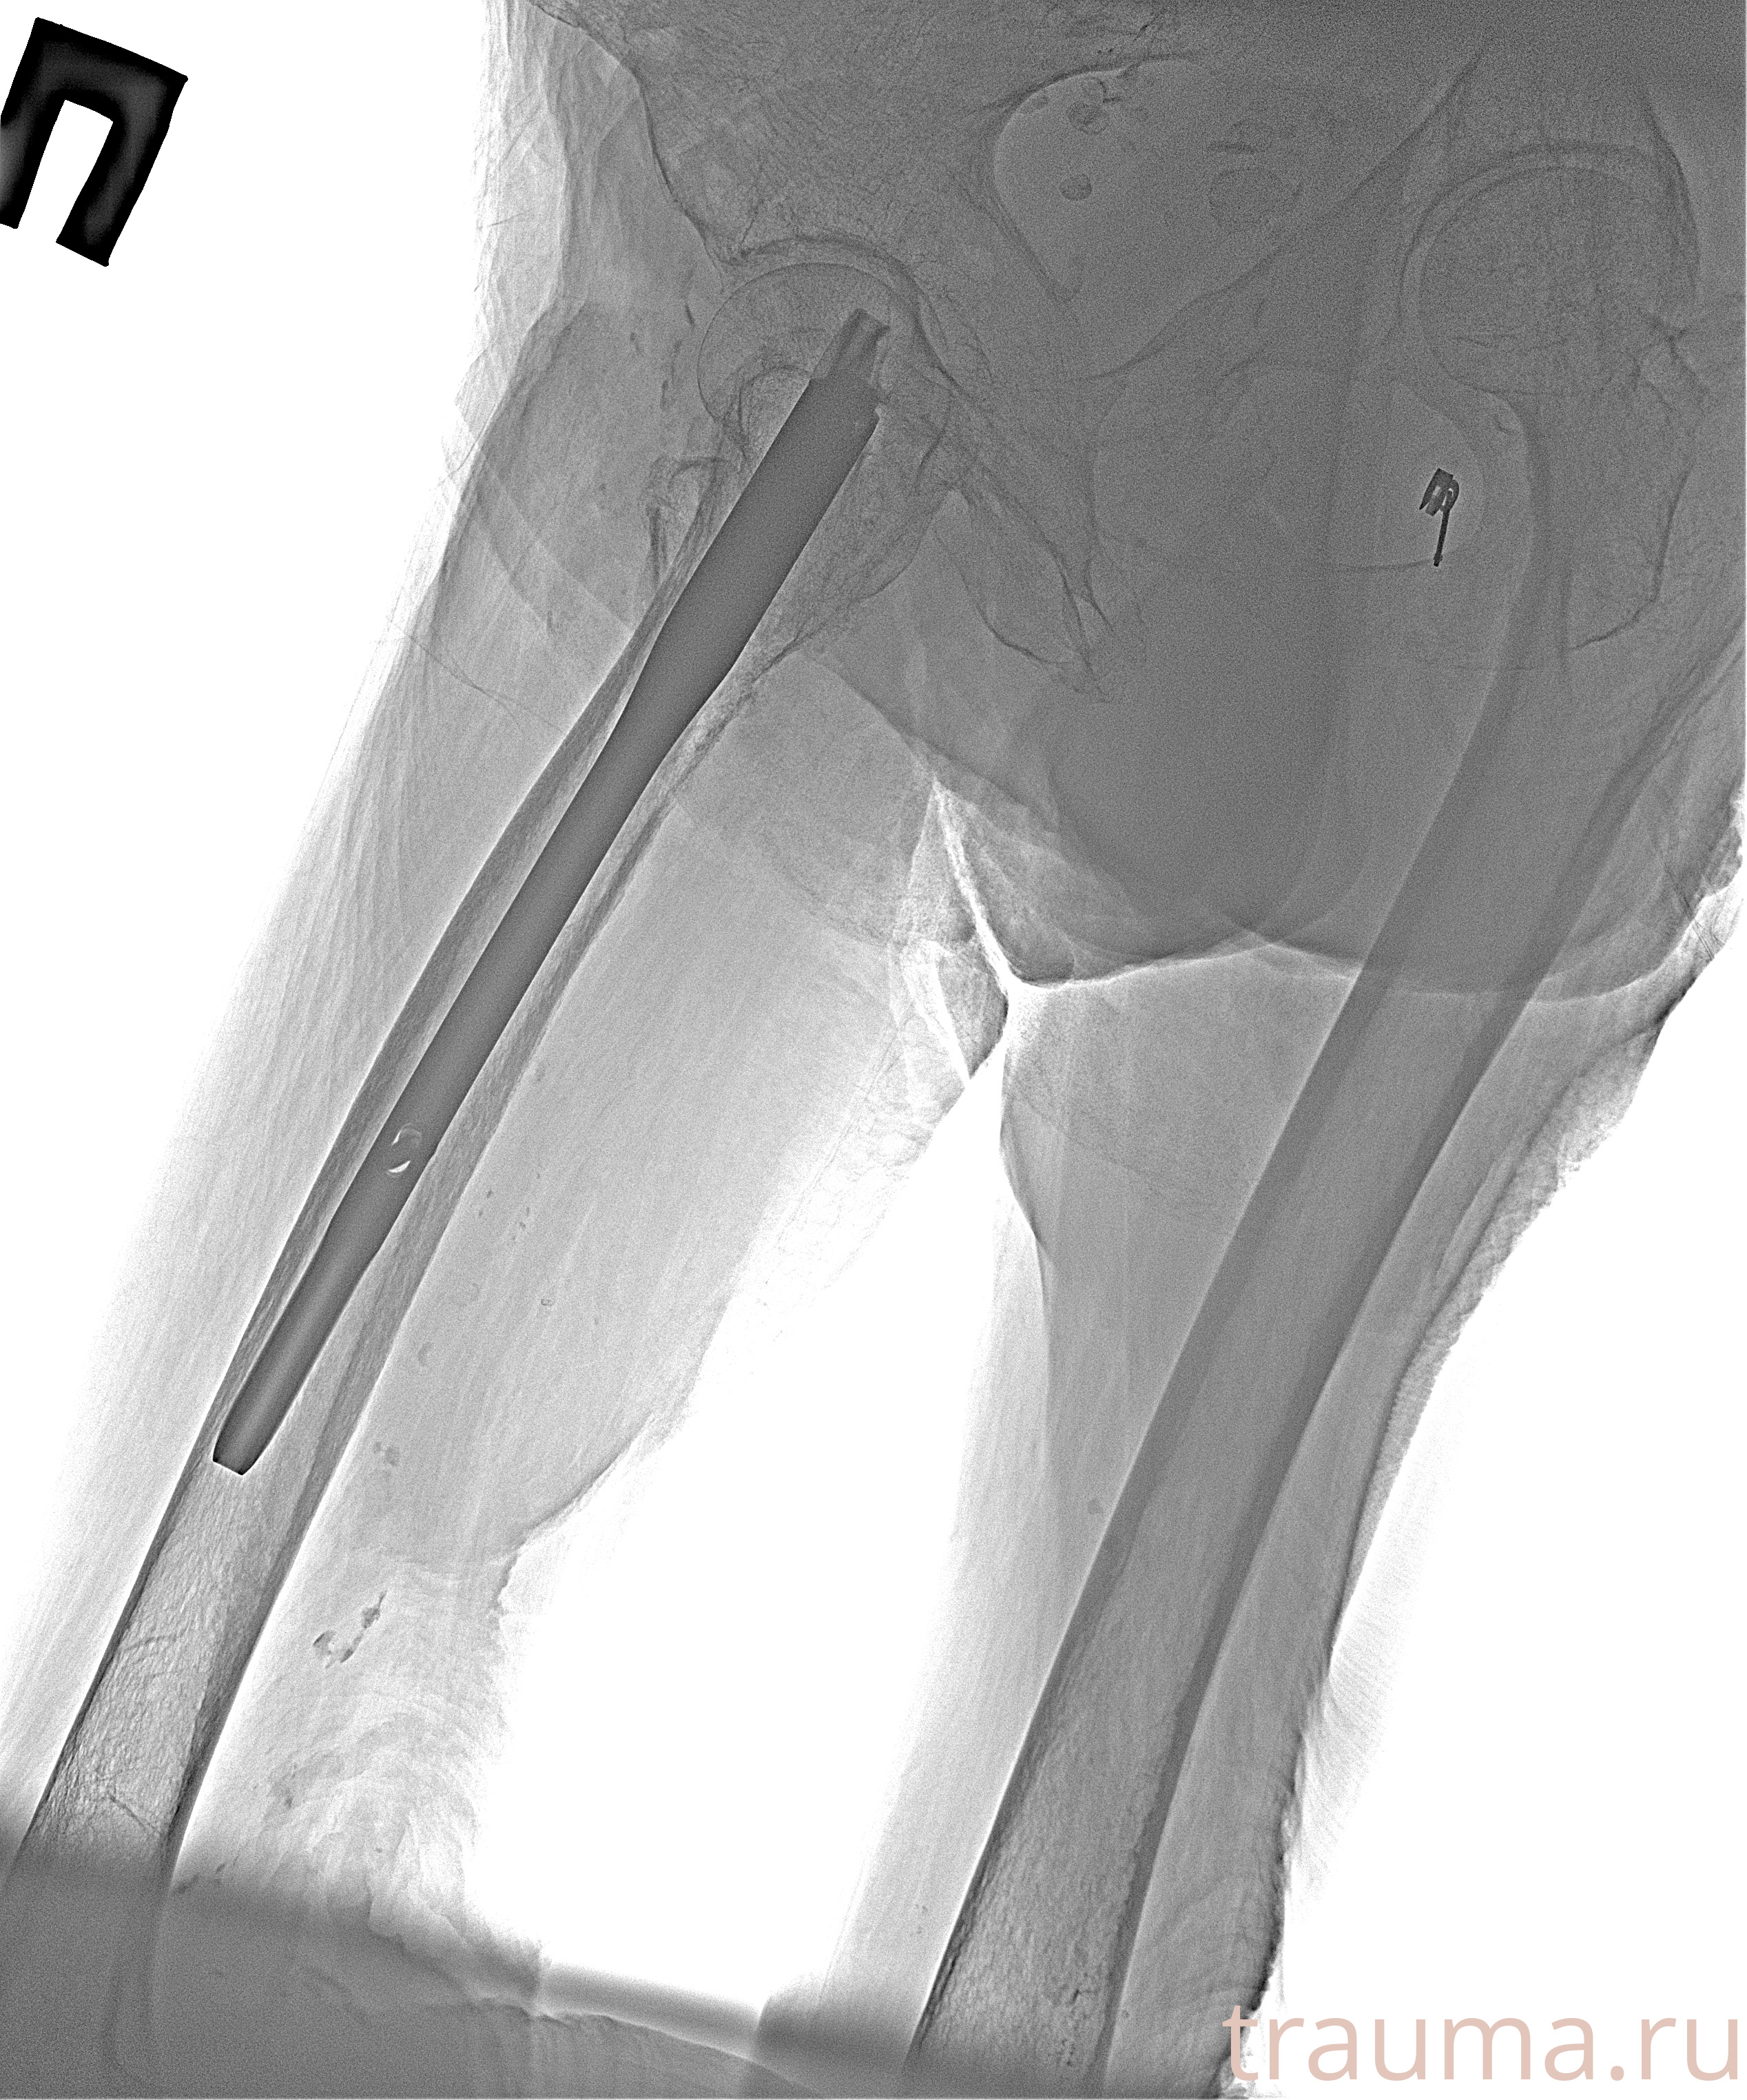

Рентгенограммы

Рентген на дому: по вашему адресу приезжает врач-рентгенолог, травматолог-ортопед с мобильным рентгеновским аппаратом, проводит диагностику травмы или заболевания, делает необходимые рентгенограммы, дает рекомендации по дальнейшему лечению. Получить качественные снимки в домашних условиях возможно благодаря уникальной методике, разработанной МосРентген Центром для института  Склифосовского